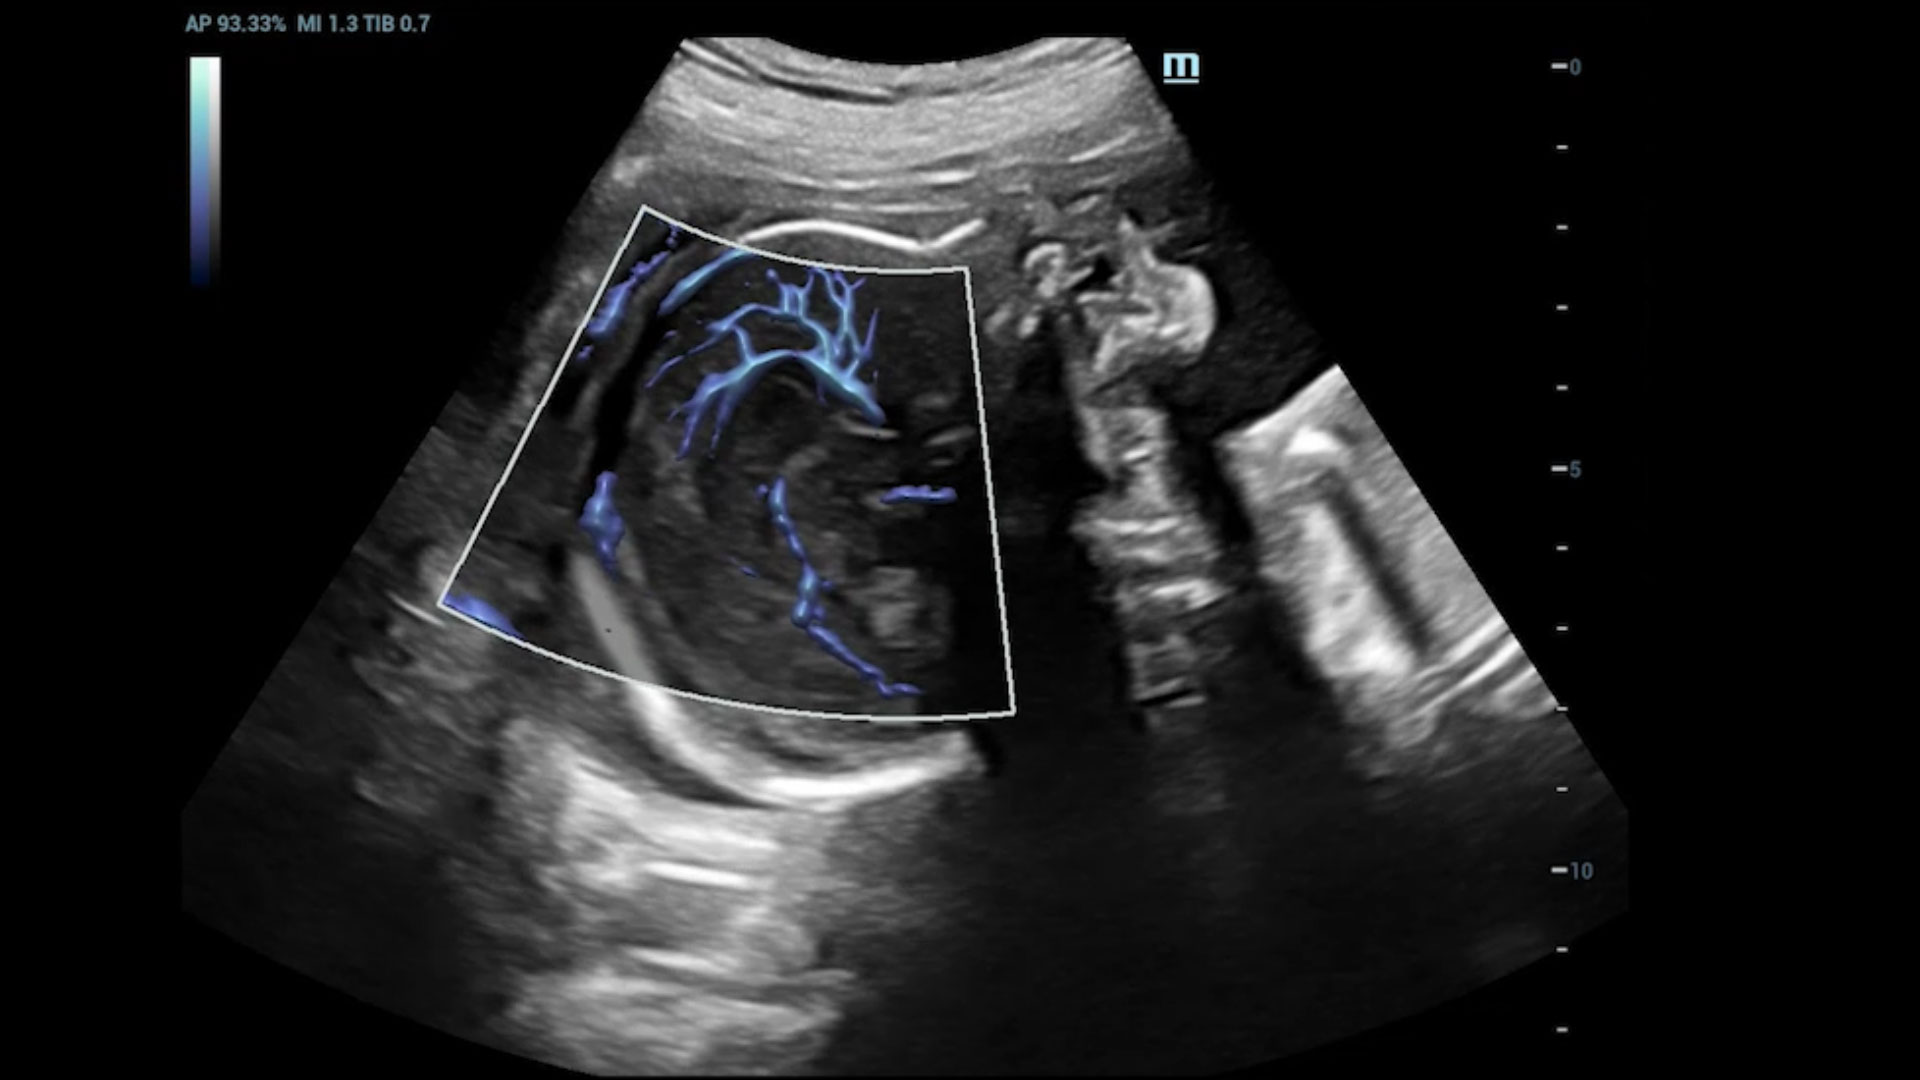

Explore mais detalhes e realidade escondida

UMA (angiografia ultramicroscĆ³pica)

A tecnologia inovadora elimina as limita??es das tradicionais imagens com Doppler. Com resolu??o espacial e sensibilidade de fluxo ultra-altas, permite a detec??o de perfus?es de fluxos muito sutis e lentos, ampliando assim a aplica??o clĆnica da avalia??o qualitativa e quantitativa do ultrassom no cĆ©rebro fetal, rins, placentas, endomĆ©trios, ovĆ”rios etc.

UMA 3D ā Fluxo intracraniano do feto